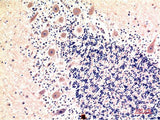

Applications IHC-p

IHC 1:100-200